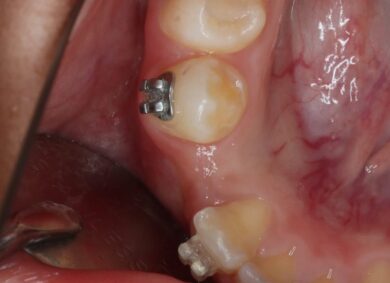

• 症例写真

①歯肉を切開して過剰歯を抜去します。

②両側の歯と骨の中に埋まっている永久歯にブラケットを装着し、ゴムの力で牽引していきます。